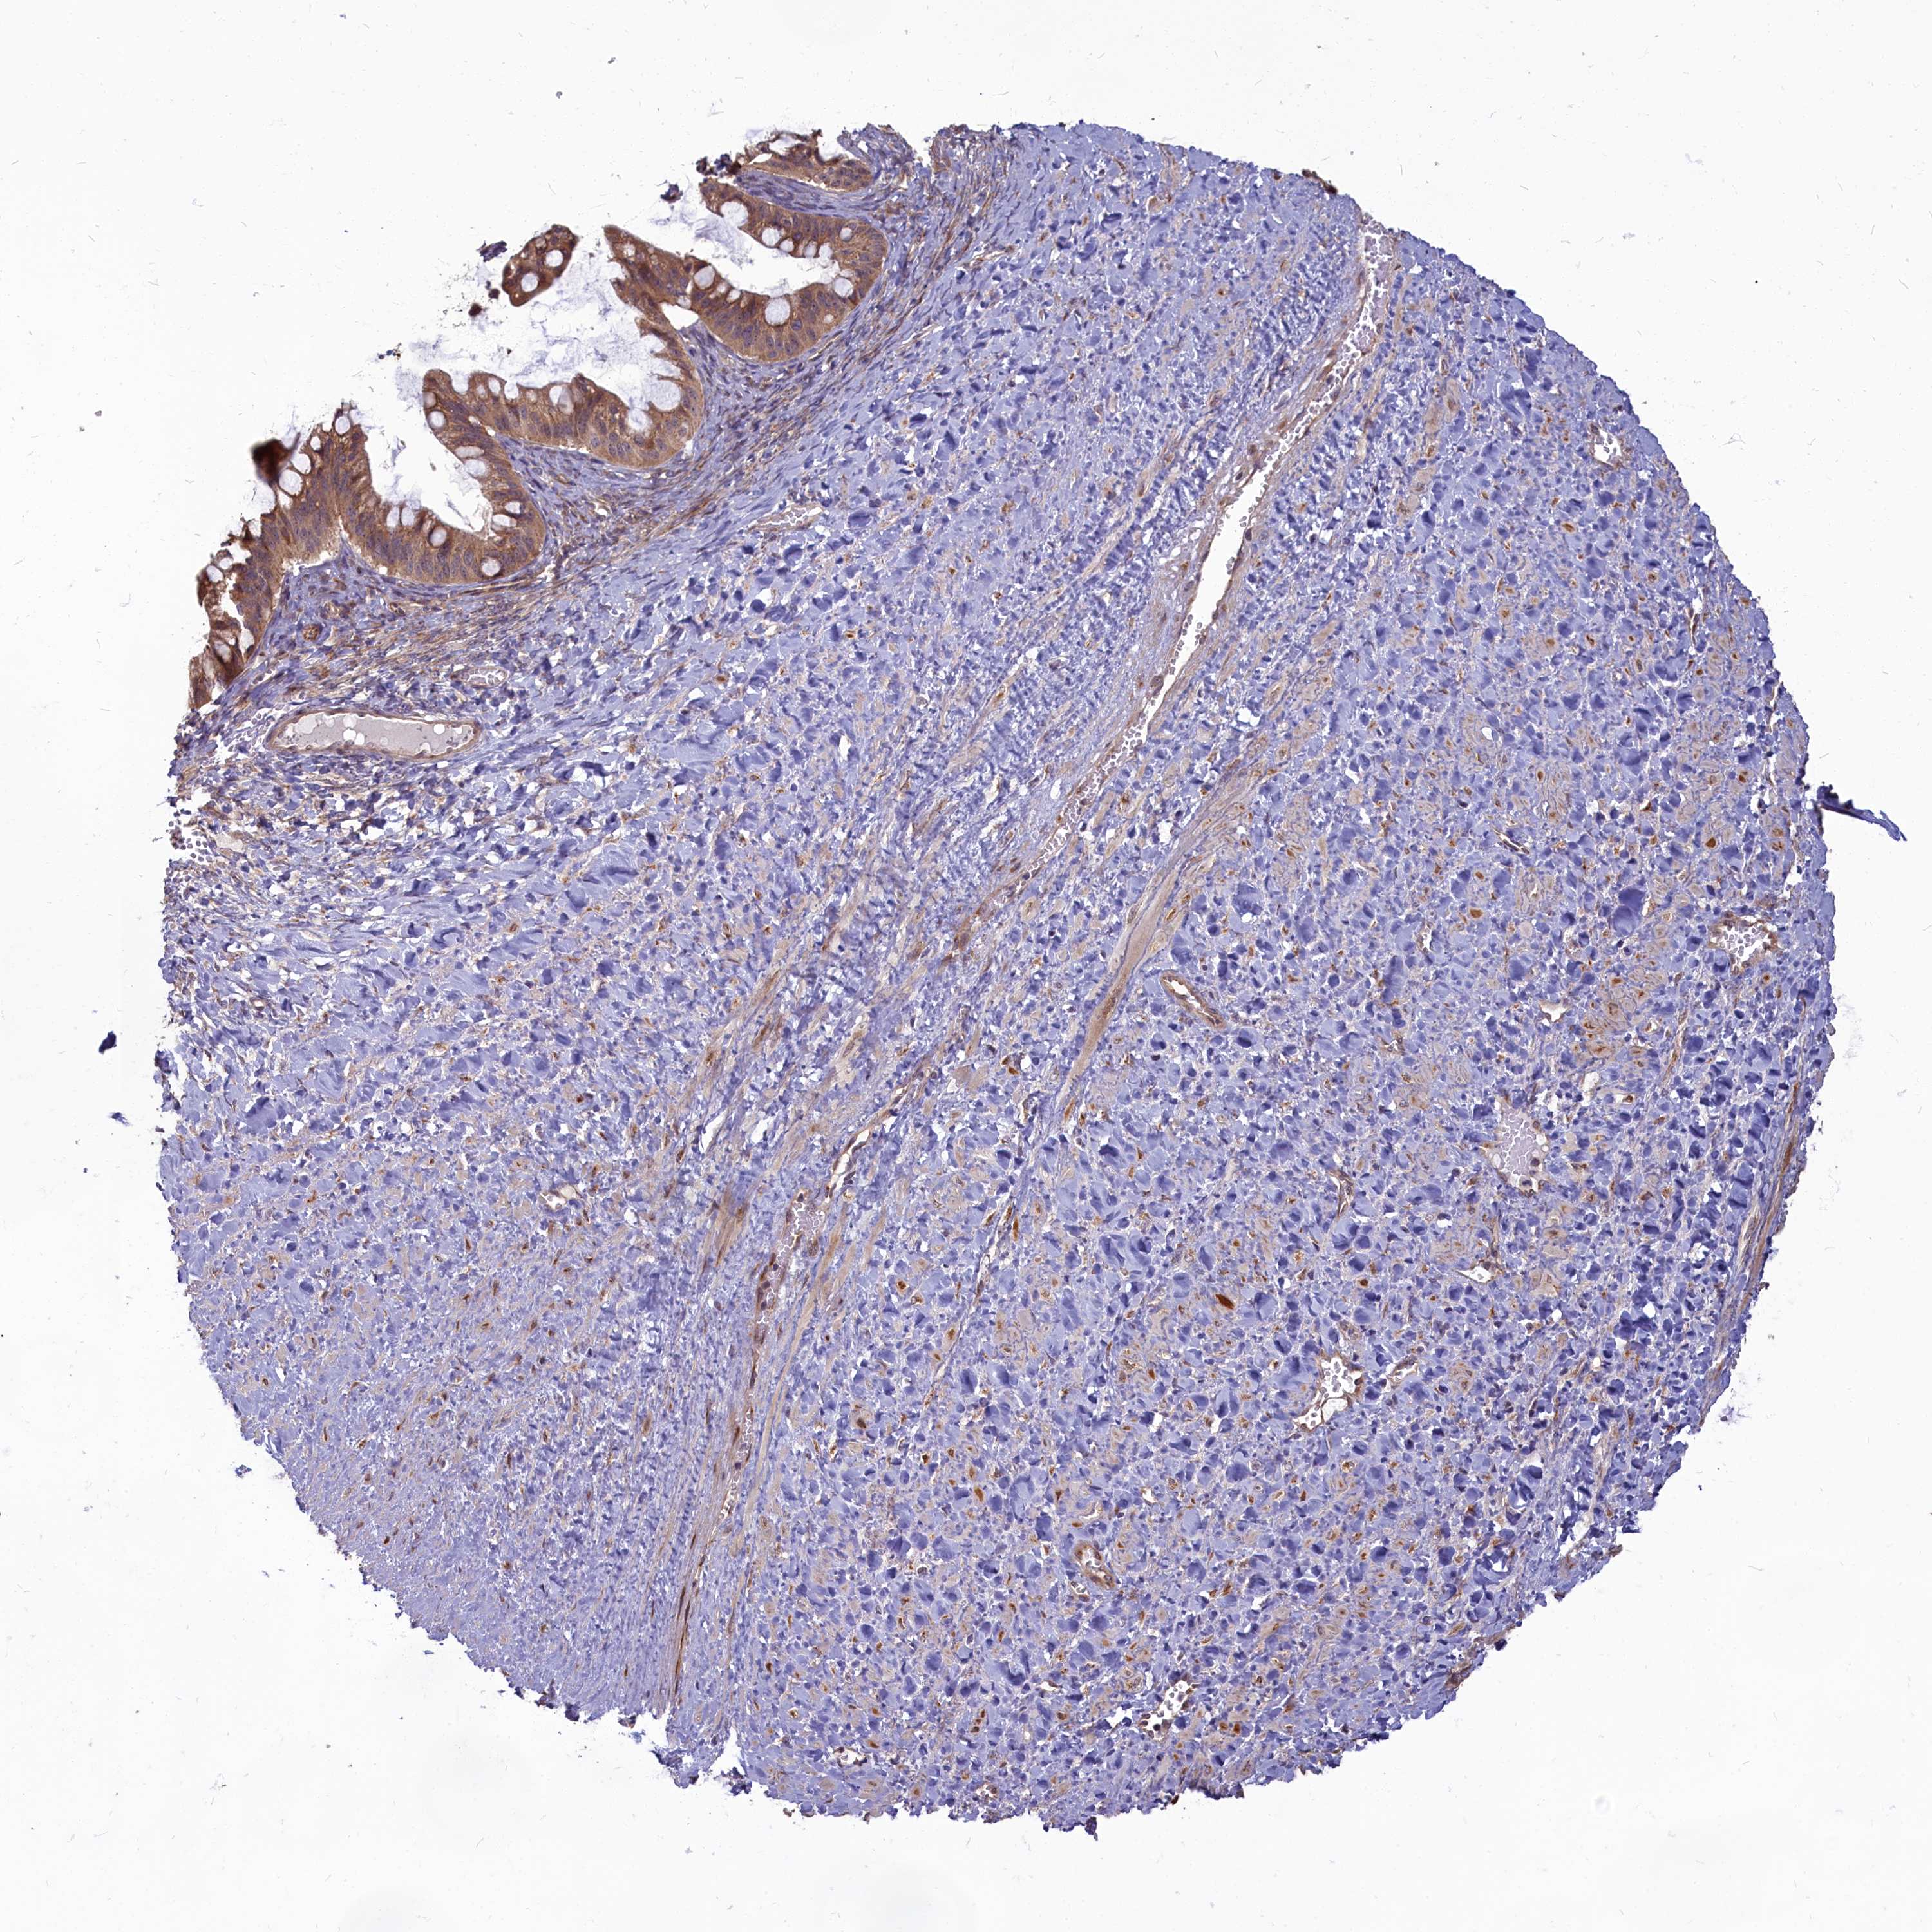

OVARIAN CANCER - Protein expressioni

A mouse-over function shows sample information and annotation data. Click on an image to view it in a full screen mode. Samples can be filtered based on level of antibody staining by selecting one or several of the following categories: high, medium, low and not detected. The assay and annotation is described here.

Note that samples used for immunohistochemistry by the Human Protein Atlas do not correspond to samples in the TCGA dataset.

Antibody stainingi

Antibody staining in the annotated cell types in the current human tissue is reported as not detected, low, medium, or high, based on conventional immunohistochemistry profiling in selected tissues. This score is based on the combination of the staining intensity and fraction of stained cells.

Each image is clickable and will lead to virtual microscopy that enables deeper exploration of all samples and also displays staining intensity scores, fraction scores and subcellular localization as well as patient and tissue information for each sample.

Antibody HPA041188

Staining

High

Medium

Low

Not detected

Intensity

Strong

Moderate

Weak

Negative

Quantity

>75%

75%-25%

<25%

None

Location

Nuclear

Cytoplasmic/membranous

Cytoplasmic/membranous,nuclear

Cystadenocarcinoma, serous, NOS

Carcinoma, endometroid

Cystadenocarcinoma, mucinous, NOS

Carcinoma, NOS